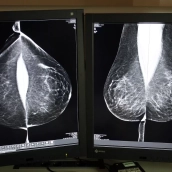

La Consejería de Sanidad vuelve a externalizar el servicio de doble lectura e informe de mamografías este año para dar respuesta a la alta cobertura del Programa de Detección Precoz de Cáncer de Mama. La licitación asciende a 1,38M€ por un año